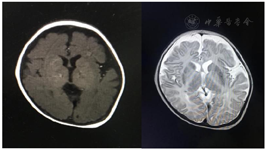

患儿,男,6岁,因"发热6 d,咳嗽、咳痰伴喘息2 d"入我院,考虑重症肺炎。患儿系其母第1胎第1产,足月剖宫产出生,出生体重4 100 g,母孕期及出生史无异常。生后即有先天性喉软骨发育不良,吃奶差伴体重不增;2月龄时患儿出现眼球钟摆样震颤,因哭吵时易发绀,完善喉镜及纤维支气管镜提示重度喉软化症(杓状软骨肥厚内收),后于新华医院行"气管镜检查+喉功能重建术";5月龄时患儿因脓毒性休克入住我院儿科重症监护病房(PICU),病程中有过抽搐史,头颅磁共振成像(MRI)示脑沟深,髓鞘发育不良(图1),完善基因检测提示佩梅病。家系成员均表型正常,父母非近亲结婚,追溯母亲三代家系均未有佩梅病史。

相关检查:入院后血常规: C反应蛋白5.8 mg/L,淀粉样蛋白A 208.9 mg/L↑,白细胞计数6.10×109/L,淋巴细胞0.192↓,单核细胞0.072,中性粒细胞0.731↑,嗜酸性粒细胞0.003↓;粪、尿常规正常;心脏超声示心内结构大致正常左心收缩功能正常范围伴少量心包积液;胸部CT示右肺感染伴少量渗出。头颅CT示两侧脑室偏大,双侧大脑半球脑沟偏深,双侧颞极脑外间隙增宽。基因测序显示患儿染色体chrX:103040600上存在PLP1基因c.94T>C(p.F32L)(图2)。

佩梅病是一种罕见的X连锁隐性性状遗传的早发性运动障碍,其特征为中枢神经系统髓鞘发育不良且不伴有神经细胞或轴突受累[4]。佩梅病主要由致病基因蛋白脂蛋白1(proteolipid protein l, PLP1)突变导致,PLP1基因缺陷可致髓鞘形成异常和少突胶质细胞死亡,最终影响大脑的正常发育。临床上以男性发病为主,主要表现为眼球震颤、进行性运动障碍、肌张力低下等。头颅MRI常表现为大脑半球、小脑和脑神经系统的中心白色物质为弥漫性T1加权低强度信号和T2加权高强度信号[5],提示脑白质髓鞘化不良。值得注意的是1岁以内的患儿由于大脑髓鞘化不充分,头颅MRI结果不具有特异性。1岁以后的患儿脑白质及内囊的髓鞘化倒退具有重要的影像学诊断价值[6]。遗憾的是,本例患儿1岁后未再做头颅MRI评估大脑发育情况。